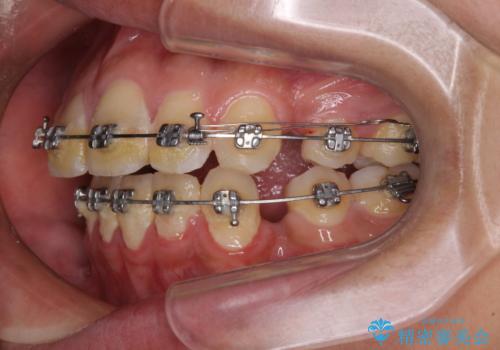

- メタルブラケット

- 2年10ヶ月

- 10-30回

小学生の頃に上顎前歯をぶつけ、歯の一部が破損している状態であったので、歯根が歯槽骨と癒着して移動しない可能性がありましたが、無事に治療を終えることができました。

受験勉強と重なり、舌のトレーニングが十分に行えず、高校生としてはやや長期間の治療となりました。